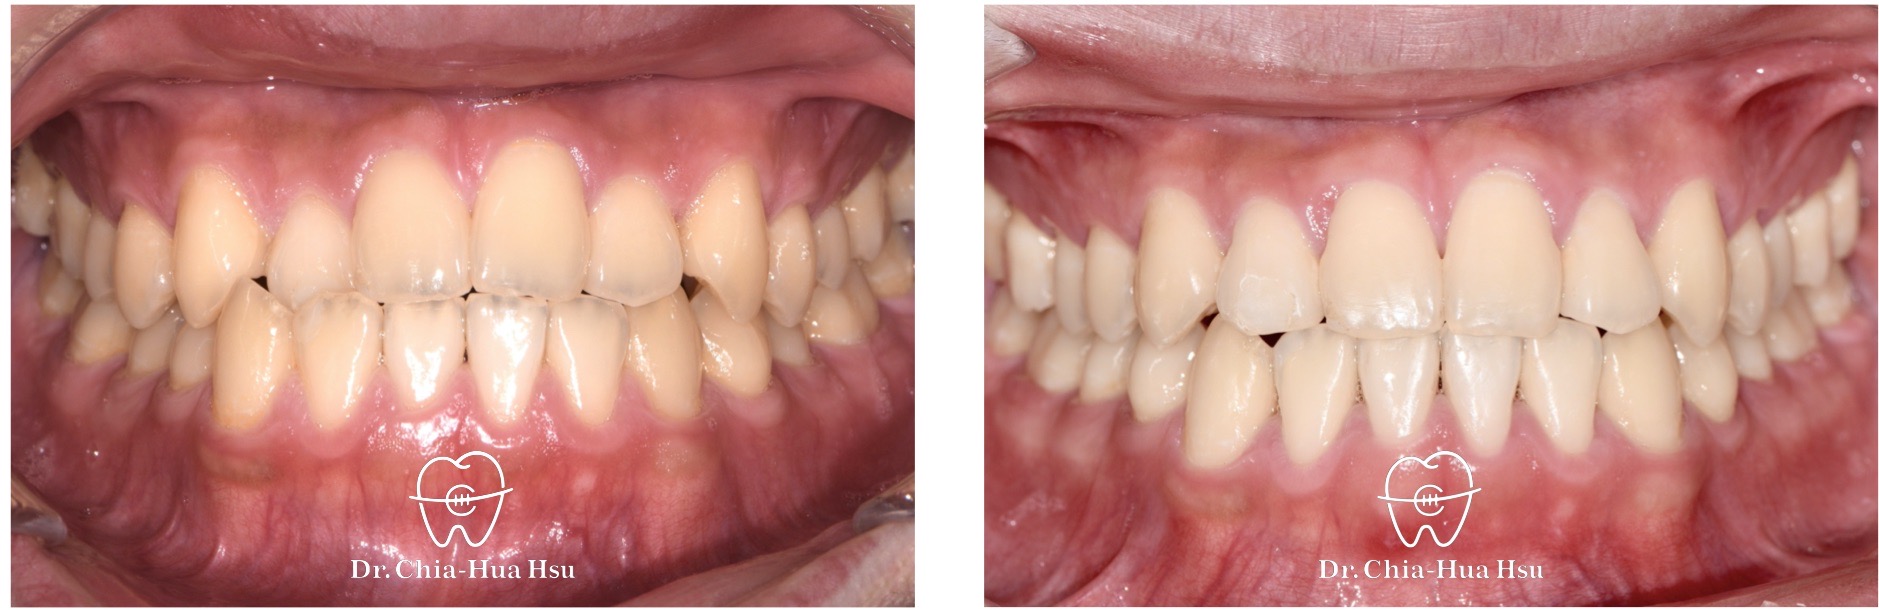

戽斗、錯咬

成人矯正 | 金屬矯正 | 非拔牙治療

• 病患主訴:前牙錯咬、不整齊,有戽斗臉型,但不想做正顎手術。

• 問題分析:患者是輕微的骨骼三類咬合(Skeletal Class III)、下巴過長(戽斗)、前牙錯咬以及齒列不整齊。

• 治療方式:使用傳統金屬矯正器,並搭配垂直向橡皮筋牽引(Vertical elastics)使牙齒萌出。

• 治療時間:2 年。

• 治療結果:門牙露出增加、齒列排齊 ; 下臉部高度微增使下巴順時針微量旋轉,以修飾戽斗臉型。

治療前

治療後